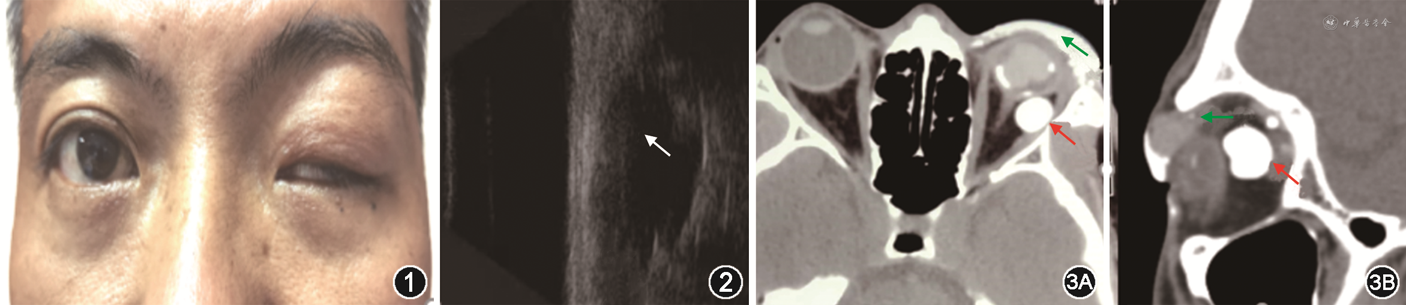

患者男性,41岁,因“左眼被铁片划伤视物不见6 h”,于2017年3月就诊于长沙爱尔眼科医院眼外伤专科,既往史无特殊,无高血压等全身疾病。眼眶CT:球内19 mm×3 mm致密异物,CT值3 071 Hu。完善术前检查后行左眼玻璃体切割、眼内异物取出、硅油填充术,术中见金属异物嵌顿于眼球壁上方,上方视网膜脉络膜裂孔,从颞侧角膜缘切口完整取出异物,术后患者顺利出院。2020年8月患者因“左眼外伤后肿胀伴睁眼困难3年余”再次就诊,眼科检查:左眼视力无光感,外斜45°,眼球各方位运动正常,睑裂高度2 mm(图1),提上睑肌肌力4 mm,角膜混浊,内眼结构窥不清。眼部B超:左眼玻璃体内强回声光团、眼球壁旁12.4 mm×15.6 mm的边界清楚的低回声区(图2),右眼轴长度23.8 mm,左眼轴长度20.2 mm。眼眶CT:左侧玻璃体、球后、眼睑下多发异常高密度影,边界清楚,CT值456~750 Hu(图3)。入院诊断:左眼眶眼睑肿物,性质待查(硅油可能性大),左眼上睑下垂,左眼硅油眼,左眼球萎缩。入院后第3天,在局部麻醉下行左眼眶眼睑肿物摘除术,术中见左眼睑皮下组织被硅油小泡弥漫浸润,提上睑肌上方3 cm×1 cm透明样硅油囊肿(图4中A),眼球壁完整,摘除眼球后方最大的囊肿,切除部分硅油小泡浸润严重的软组织。术后眼睑肿胀明显改善,睑裂高度约6 mm。病理提示送检物为薄壁纤维囊壁组织,伴小血管,内容物清亮(图4中B)。随访1周,患者上睑稍凹陷,上睑下垂改善。